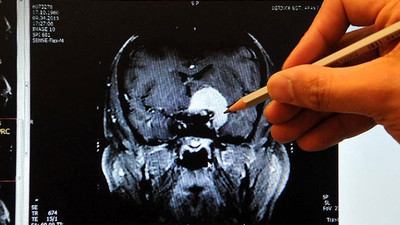

Dünyada ve Türkiye’de 2020 yılında pandemi nedeniyle getirilen kısıtlamalar nedeniyle grip vakalarına ender olarak rastlandığını belirten Türk Toraks Derneği Solunum Sistemi Enfeksiyonları Çalışma Grubu Başkanı Prof. Dr. Füsun Eyüpoğlu, risk gruplarındaki kişilerde grip enfeksiyonuna yatkınlığın artacağını ve hastalığın kliniğinin daha ağır seyredebileceğini belirterek, “Zatürre, solunum yetmezliği, nörolojik ve kalple ilgili komplikasyonlar gelişerek, ölüme neden olabilmektedir” dedi.

Milliyet'ten Meltem Günay'ın haberine göre; Prof. Dr. Eyüboğlu, risk grubundaki bireyleri de şöyle sıraladı: “5 yaş altı (özellikle 6 ay-2 yaş arası) çocuklar ve 65 yaş üzeri erişkinler, gebeler özellikle son üç ayı ekim-mayıs arasında geçecek olanlar en riskli grup, bağışıklığı baskılanmış kişiler, altta yatan kalp, böbrek, akciğer, sinir sistemi hastalığı olanlar, obez kişiler, diyabet gibi metabolik hastalığı olanlar, 18 yaş altında olup sürekli aspirin kullanmak zorunda olanlar, kendileri influenzanın ağır seyretme riski taşımasalar da yukarıdaki risk grupları ile yakın temasta olan kişiler ve sağlık çalışanları.”

COVİD-19 İLE KARIŞTIRMAYIN

Türk Toraks Derneği Genel Başkanı Prof. Dr. Oya İtil de grip ve Kovid-19’un nasıl ayırt edilebileceği hakkında bilgiler verdi. Prof. Dr. Oya İtil grip belirtilerinin de Kovid-19 ile çok benzer olduğuna dikkat çekerek şunları söyledi: “Ani başlangıçlı ateş öyküsü, öksürük veya boğaz ağrısı en tipik bulgularıdır.

Kas ağrısı, kırgınlık ve baş ağrısı, solunum sıkıntısı da eşlik edebilir. Bu bulgular Kovid-19 ve diğer viral solunum yolu enfeksiyonlarına benzerdir. Grip virüsü en sık öksürme, hapşırma ile ortama saçılan damlacıklar yoluyla insandan insana bulaşır. Hastalık, okul öncesi ve okul çağı çocuklarda daha hızlı yayılır.

Okulların açılması ile önümüzdeki dönemde grip enfeksiyonunun toplumda yayılım hızında artış beklenmekte. Belirtiler başlamadan 24 saat önce bulaştırıcılık başlar, sonraki 5-7 gün bulaştırıcılık devam eder. Genellikle gribin klinik belirtileri 1-2 hafta içinde tamamen düzelmektedir.”